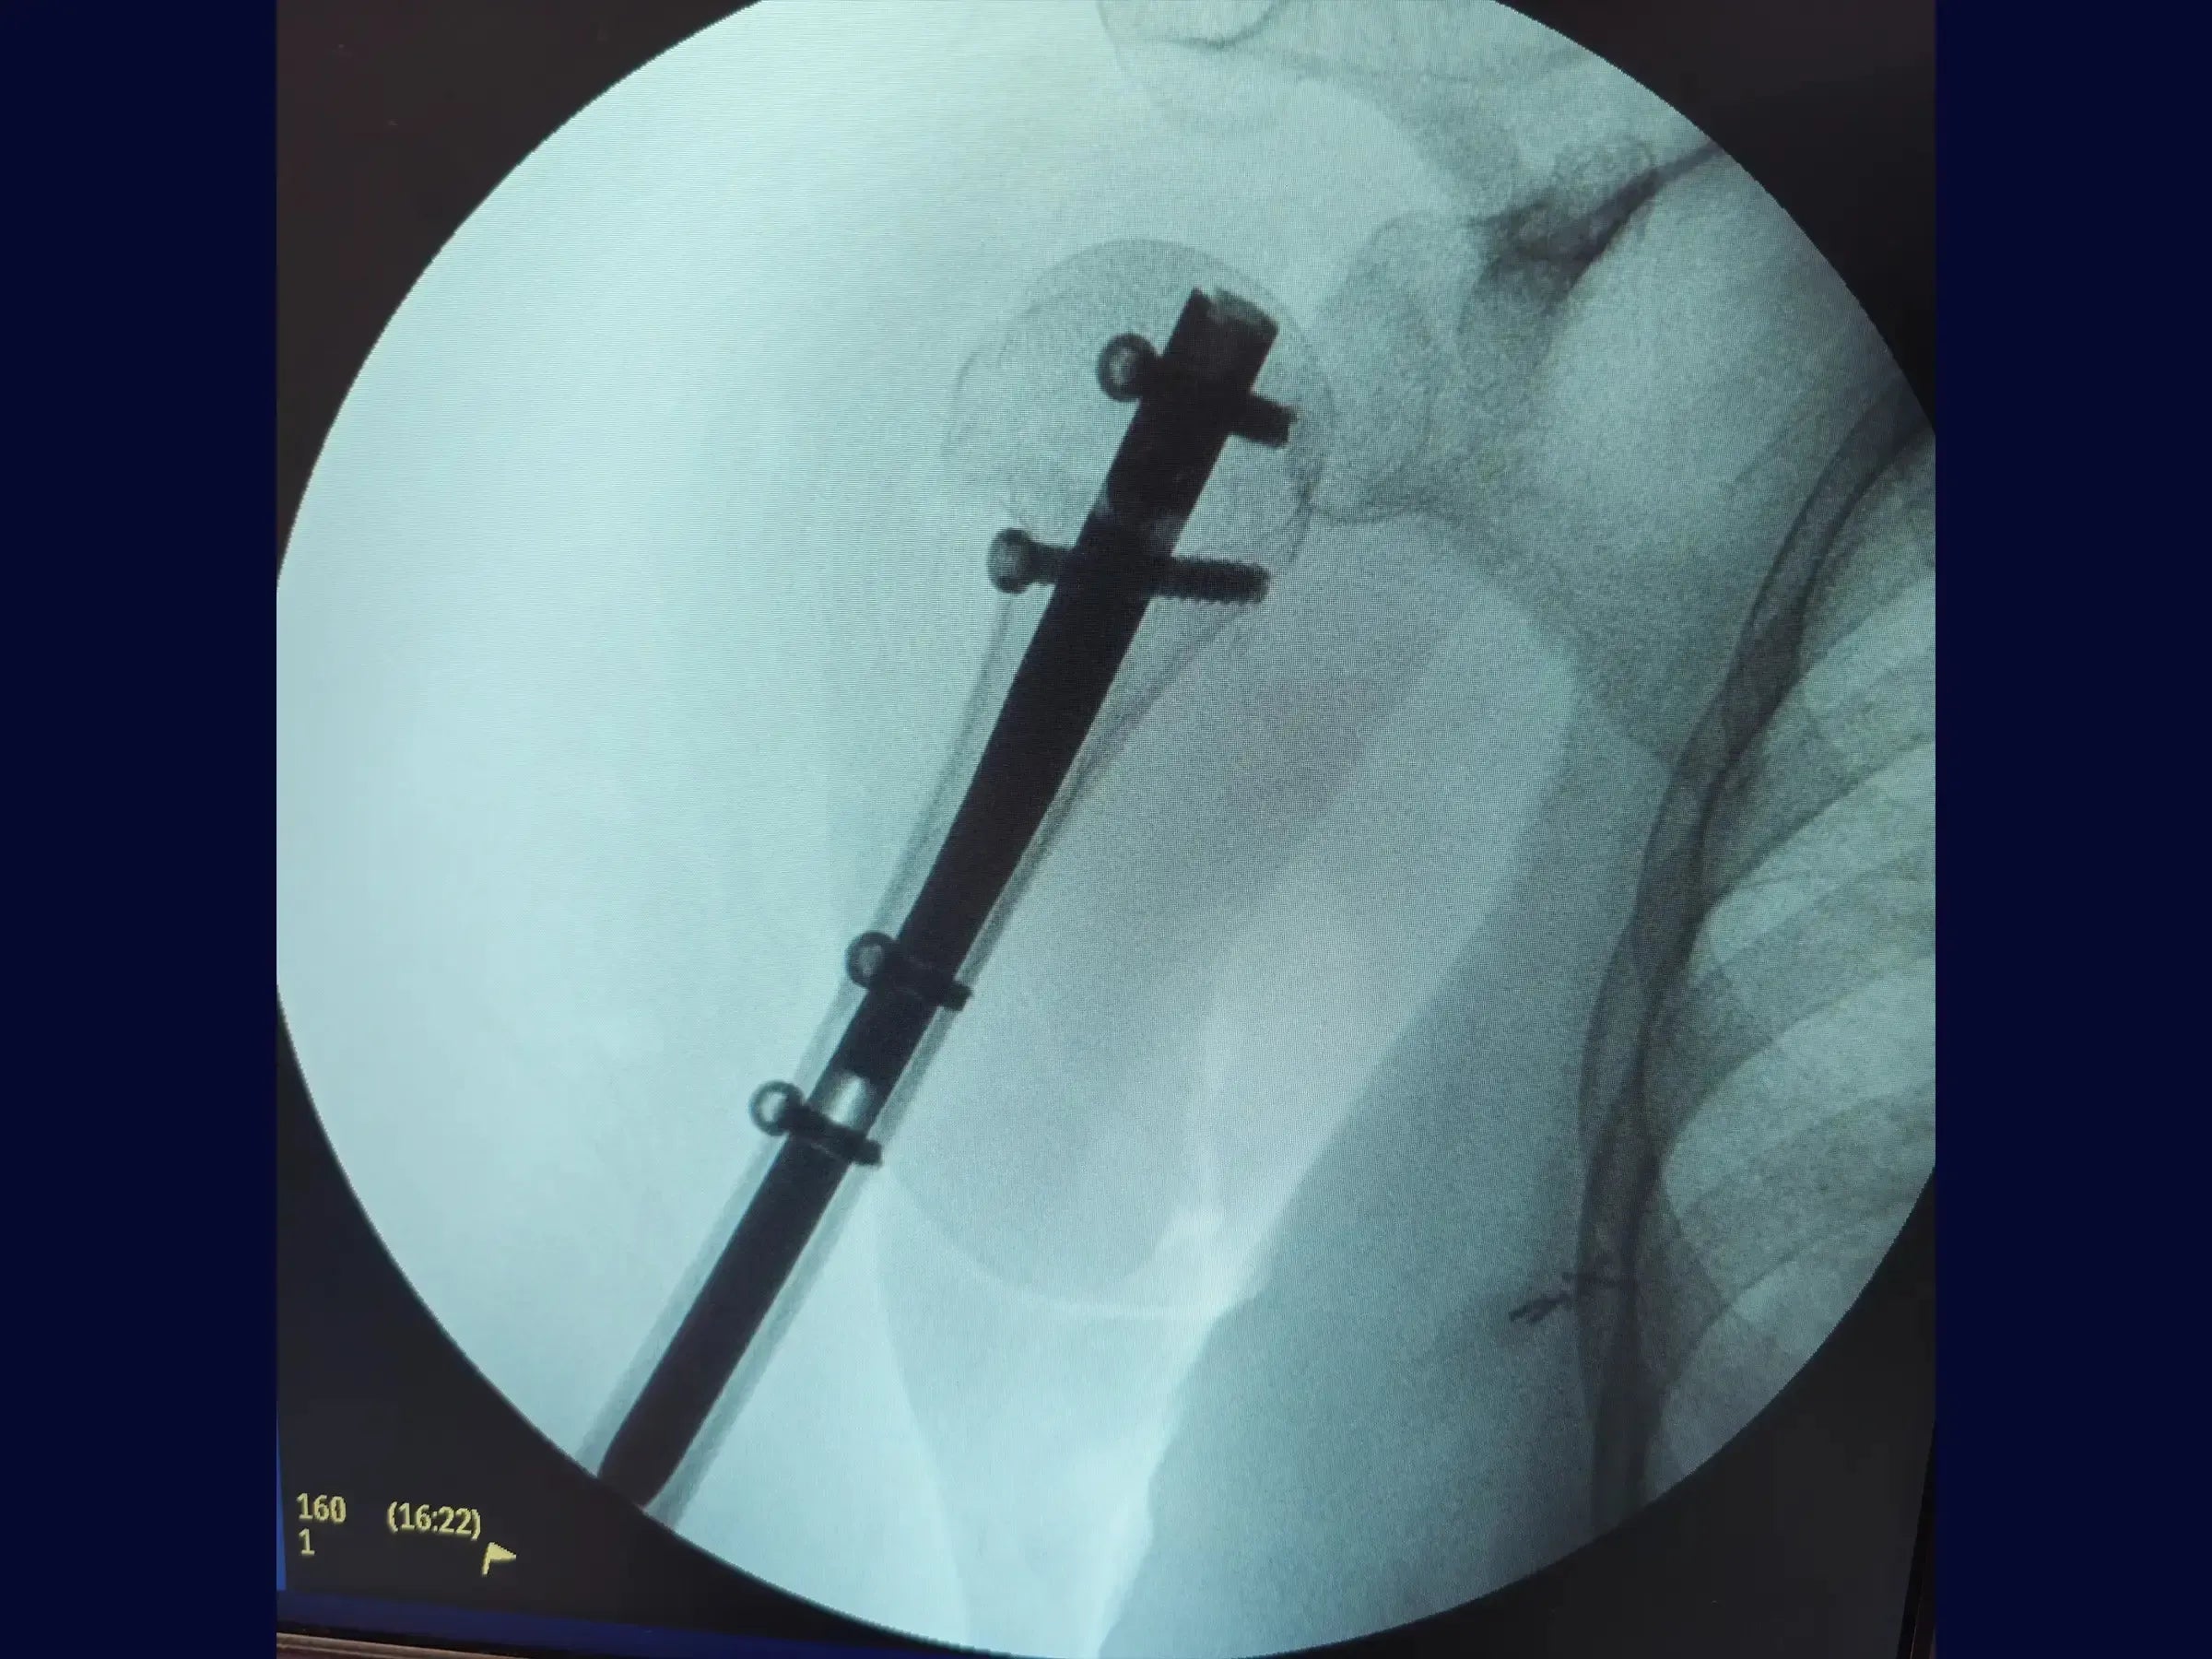

Haste Intramedular para Fratura do Úmero Proximal

A complexidade das fraturas do úmero proximal exige abordagens que preservem a função e minimizem a morbidade. Este treinamento oferece uma imersão técnica na osteossíntese com haste intramedular, utilizando acessos minimamente invasivos e uma técnica de manipulação do fragmento proximal com "joystick", focando na recuperação do eixo, rotação e versão da cabeça umeral sem a necessidade de uma redução anatômica precisa.

- Otimização da Introdução do Fio Guia: Estratégias para posicionamento preciso do fio guia na cabeça umeral, auxiliado por conferência radiográfica e pelo uso do "joystick" para obter imagens AP e lateral.

- Mensuração Precisa da Haste Intramedular: Protocolos de mensuração utilizando um guia externo, com atenção às particularidades anatômicas do úmero distal para evitar subdimensionamento ou sobredimensionamento do implante.

- Técnica de Inserção da Haste Intramedular: Abordagem para introdução manual da haste, visando prevenir o uso de martelo e reduzir o risco de fraturas iatrogênicas.